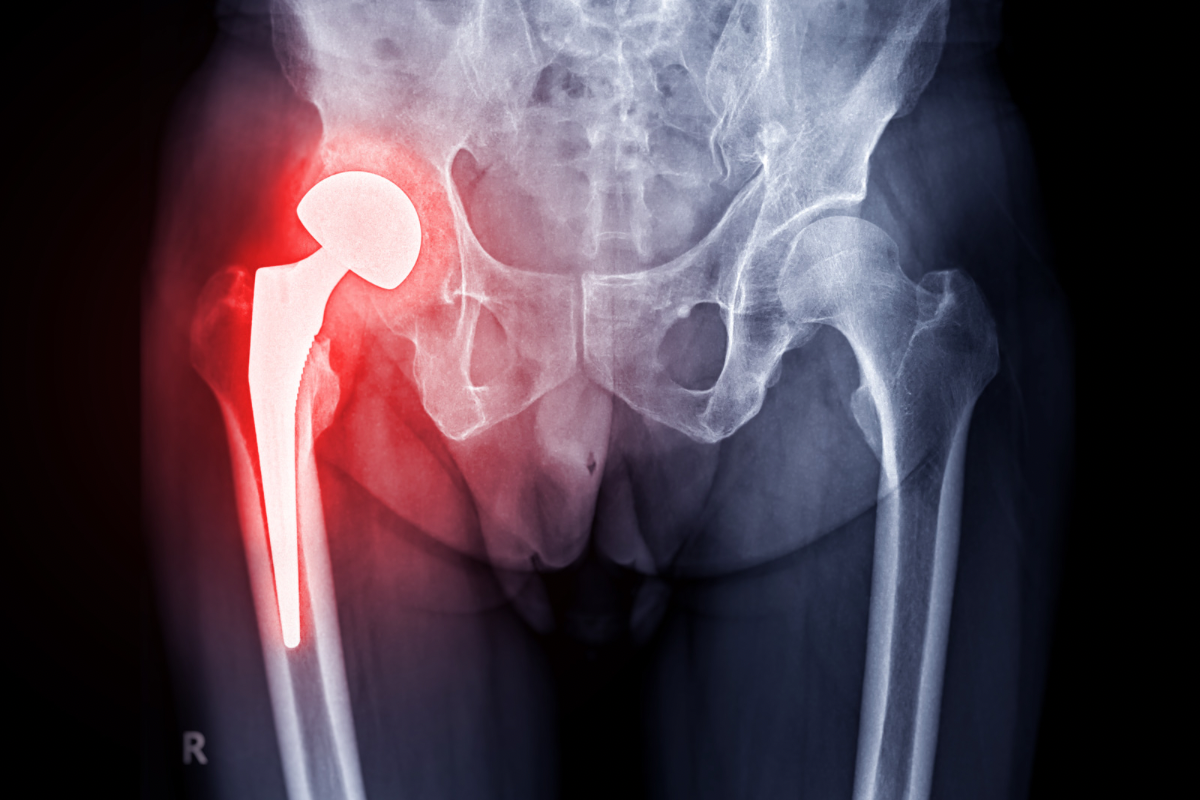

Kinetoterapia pentru recuperarea după leziuni și intervenții chirurgicale ale șoldului

În cazul leziunilor grave sau intervențiilor chirurgicale ale șoldului, kinetoterapia joacă un rol esențial în recuperarea completă și rapidă. După o fractură de șold, protezare sau alte tipuri de intervenții chirurgicale, kinetoterapia ajută pacienții să își recâștige mobilitatea și să prevină complicațiile postoperatorii. Exercițiile post-operatorii sunt esențiale pentru a sprijini procesul de vindecare, pentru a întări mușchii care susțin articulația și pentru a restabili funcționalitatea. Kinetoterapia postoperatorie include atât exerciții ușoare, pentru început, cât și tehnici mai avansate pentru pacienții care sunt într-un stadiu mai avansat de recuperare. Scopul este de a preveni rigiditatea și de a ajuta pacientul să își îmbunătățească mobilitatea cât mai rapid.